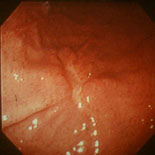

早期胃がん |

進行胃がん |